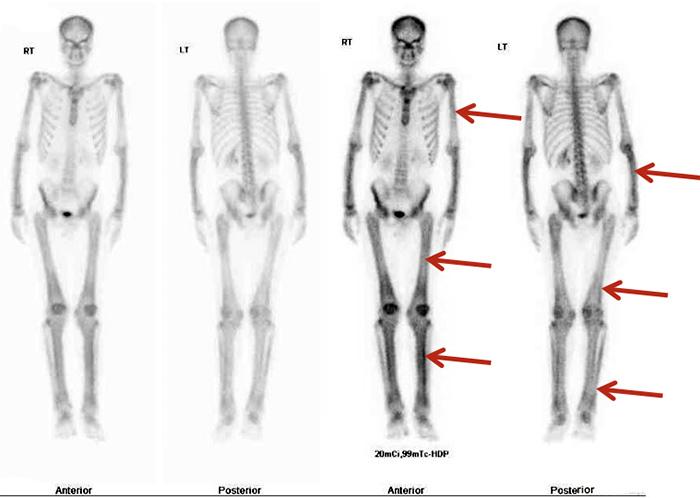

We described the case of a 23-year-old Nepalese man with seropositive rheumatoid arthritis and abnormal x-ray findings, found to be due to a very rare bone disease: Camurati Engelmann disease or progressive diaphyseal dysplasia (PDD). This is the first case reported in the Gulf area, although approximately 300 cases have been described worldwide. These patients usually present with limb pain and easy fatigability. Our patient first presented with bilateral, symmetrical inflammatory polyarthritis involving the knees, ankles and wrists but sparing the hands and feet. The diagnosis of PDD in our case was based on the classic radiological findings and a bone scan.

我们描述了一名23岁尼泊尔男性的病例,他患有血清阳性类风湿关节炎且X线检查结果异常,后来发现是由一种非常罕见的骨病引起的:卡穆拉蒂-恩格尔曼病或进行性骨干发育异常(PDD)。这是海湾地区报道的首例病例,尽管全球已描述了约300例。这些患者通常表现为肢体疼痛和易疲劳。我们的患者最初表现为累及双膝、双踝和双腕的双侧对称性炎性多关节炎,但手部和足部未受累。我们病例中PDD的诊断基于典型的放射学表现和骨扫描。